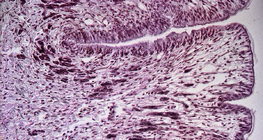

400倍の倍率

倍率100倍